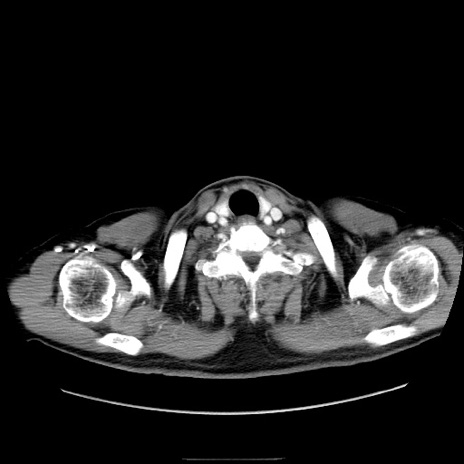

症例30(横断像)

【症例】80歳代男性

【主訴】臍周囲痛

【現病歴】約6時間前から臍下部痛が出現。次第に腹部膨隆・背部痛も生じてきたため来院。背部痛の場所は変化しない。

【身体所見】意識清明、BT 36.3℃、BP  131/87mmHg、P 87bpm、SpO2 100%(RA)、臍周囲自発痛・圧痛あり、反跳痛なし、自発痛部位に一致して板状硬あり、腹部膨隆、腸雑音減弱、CVA tenderness両側陰性。